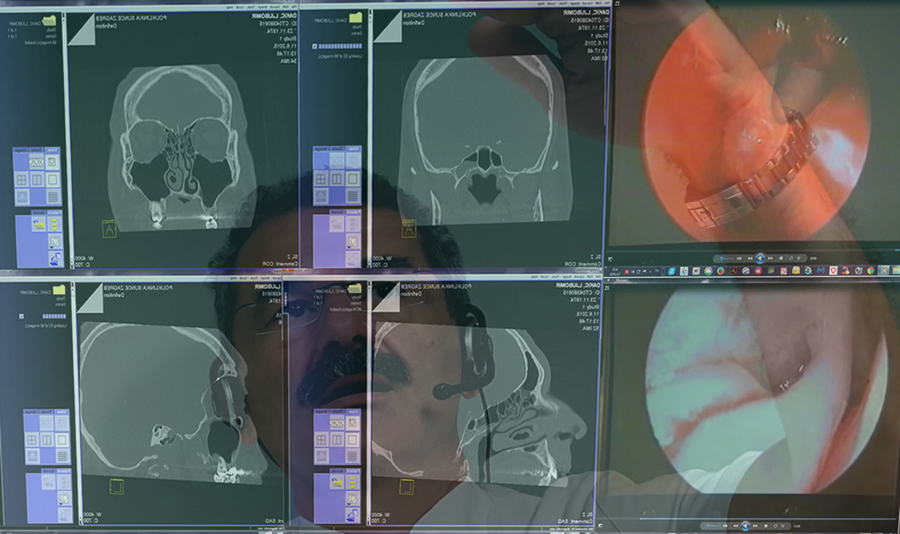

LeapMotion and OsiriX 1

Simulated 3D-reconstruction of organs from MSCT-cross sections is an important diagnostic tool by providing clinicians with a more naturalistic view of a patient's anatomy; the interactivity reflects in the possibility of simulating the endoscope tip movements through an organ cavity, or empty spaces (virtual endoscopy or virtual surgery), and the real-time requirement means that the simulation must be able to follow the actions of the user that may be moving in the virtual environment as seen in the operating room in the surgical department of the Klapan Medical Group Polyclinic.

Virtual endoscopy 1

Virtual endoscopy: any surgeon is concentrated on the surgery being performed, and after he makes a decision to use VE, he doesn't think about the hand position which should be used when entering the active area (closed fist, indicating for inactive state). Osirix/Leap Motion/Bitmedix plug-in 3D-navigation surgery in rhinology (with "commands in the air") supported by virtual endoscopy and virtual surgery. Navigating through narrow pathways in VE, we noticed that the camera can stray into the tissue. Following that, getting back on track seemed hard, sometimes even impossible without going back to the starting position, as seen (in the test phase, during intraoperative analysis) in the operating room in the surgical department of the Klapan Medical Group Polyclinic).

Virtual endoscopy 2

Virtual endoscopy: navigation endoscopic sinus surgery with virtual endoscopy (VE), virtual surgery (VS) as seen (in the test phase, in the operating room) in the surgical department of the Klapan Medical Group Polyclinic; using this approach, the surgeon can use swipe-like gestures for positioning which are more natural to humans than sign gestures. In many cases, when entering sensor active area, the surgeon would keep an open hand (active state) which mostly resulted with sudden change in position and loosing orientation in space.